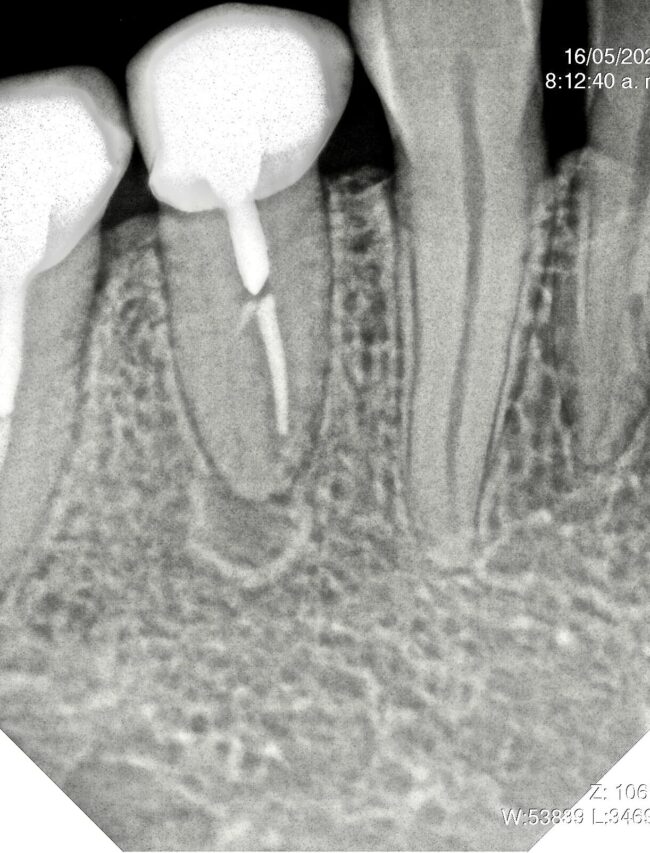

Dr. Marc Llaquet’s clinical case of a reendodontic tooth 2.4 instrumented with RetreatAll® files to remove gutta-percha in which ultrasonic activation was performed with Z-Activator® during irrigation.